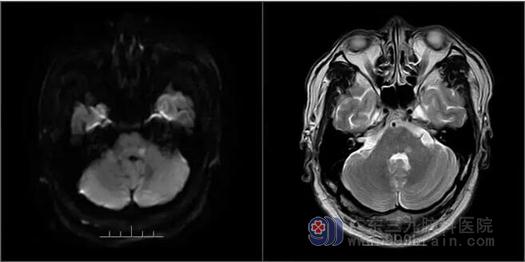

▲患者MR检查

我院院长助理、神经内一科主任王展航接诊后,为患者完善了相关检查。患者的MR检查显示延髓左侧有斑点状的异常阴影。结合检查结果和临床病症,最终明确钱某此次发病为延髓梗塞。